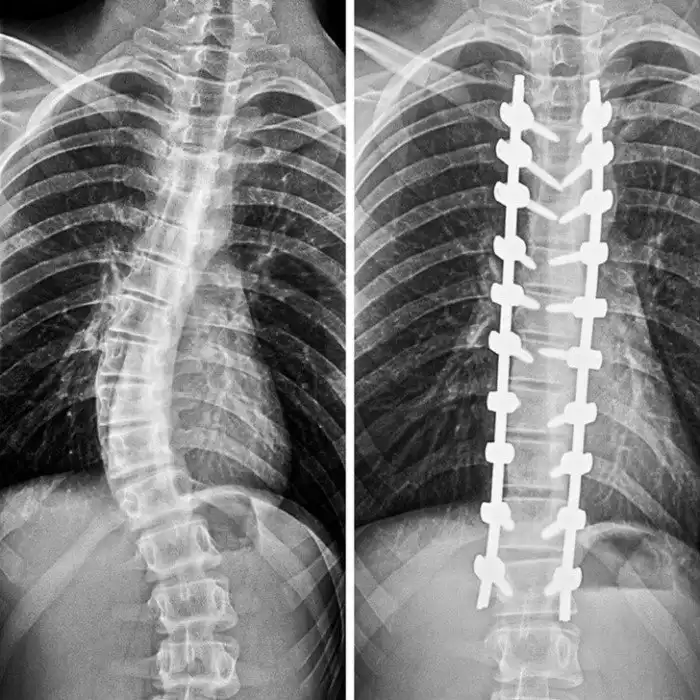

Так выглядит позвоночник после коррекционной операции при сколиозе.